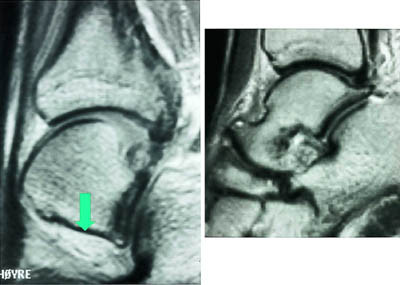

Mesteparten av sinus tarsi er fylt med fett. Dette gir høysignal på T1-vektet sekvensog lavsignal på fettsuppresjonssekvenser. Blodkar og nervefibrer gir små punktformige lavsignaler medialt i fettvevet på T1-vektet sekvens. Ligamentene gir lavsignal på spinnekkosekvensene. Figur 1 viser en normal sinus tarsi. I koronalplanet sees ligamentum cervicale ventralt og ligamentum interosseus noe lenger dorsalt. Det mest fremtredende og hyppigste MR-funnet ved sinus tarsi-syndrom er lavsignalområder på T1-vektet sekvens og lav- eller høysignalområder på T2-vektet sekvens. Forandringene er forårsaket av fibrose (fig 2) med eller uten inflammasjon (fig 3). Av og til kan vi se små væskelokulamenter som representerer ganglioncyster (fig 4). Ligamentene kan være vanskelig å se, enten fordi det er mye inflammasjon eller fordi de er røket. Hos en del pasienter kan man finne ruptur av laterale ankelligamenter, spesielt ligamentum talofibulare anterior.